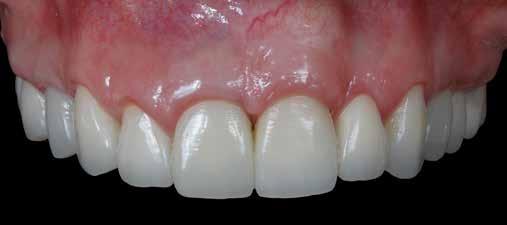

Az oxigén inhibíciós réteg kialakulásának elkerülése érdekében a kerámiafelszíneket glicerin géllel (Liquid Strip, Ivoclar Vivadent, Schaan, Liechtenstein) borítottuk, majd ezeket a felszíneket ismét 20-20 másodpercen keresztül világítottuk. A végeredmény megfelelt a páciens esztétikai igényeinek (6. a. ábra). Az átadott restaurátumok épségének megőrzése érdekében, a páciens számára éjszakai fogvédő sín készült. Az ötéves kontroll alkalmával megállapítottuk, hogy az elvégzett kezelésünk továbbra is sikeresnek tekinthető (6. b. ábra)

Az általunk alkalmazott adhezív rendszerek hatékonyságát nagymértékben növelhetjük azáltal, hogy a fogakat minimál invazív módon, azaz csak zománcon belül preparáljuk, és a kerámia héjakat kofferdám izolálásban ragasztjuk. Jelen esetismertetésünknek az volt a célja, hogy bemutassuk, hogyan lehet az adekvát módon kivitelezett kofferdám izolálással megelőzni

a munkaterület nyállal, vérrel vagy szulkusz-váladékkal történő kontaminációját. A megfelelő méretben kialakított perforációs nyílások és köztük lévő optimális távolság elengedhetetlen ahhoz, hogy a kofferdámot ideális módon tudjuk felhelyezni. Ezzel az esettel azt is bizonyítjuk, hogy a gumilepedő levegőfújással, fogselyemmel és teflonszalagok segítségével történő beforgatásával az ínyvérzés kialakulását el lehet kerülni. Ismételten szeretnénk hangsúlyozni, hogy a megfelelő kofferdám kapcsok használata nélkül nem tudtuk volna a preparált csonkszélt a gumilepedő szélétől eltartani. A kezelés során elért eredményeket jól alátámasztotta, hogy a páciens az ötéves kontroll vizsgálat során teljesen elégedett volt.